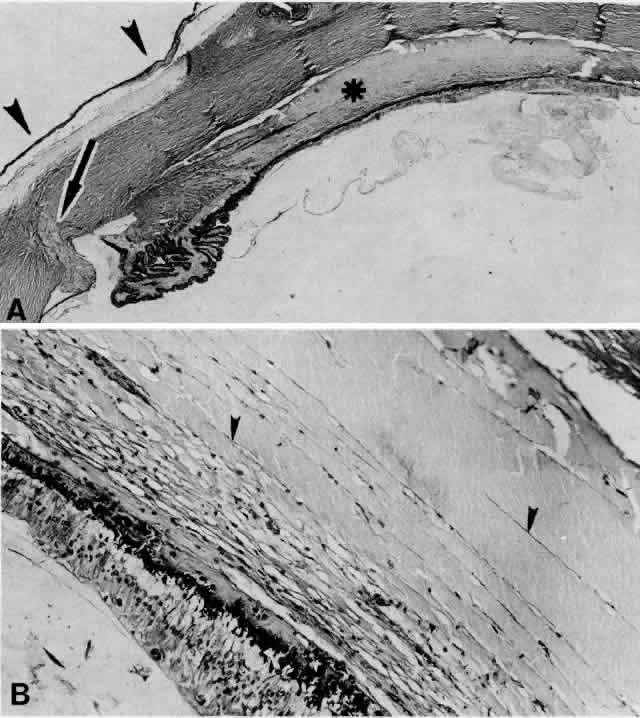

The literature does not clearly distinguish between uveal effusion syndrome and idiopathic ciliochoroidal effusion.9,65 They may most likely represent the same entity. In fact, findings similar to those for uveal effusion syndrome have been described in eyes with idiopathic ciliochoroidal effusion (Figs. 19B and 20C and D). An idiopathic ciliochoroidal effusion, however, is considered clinically and pathogenetically different from an effusion in a nanophthalmic eye, which is small and chronically hypotonous.89

Fig. 19. A. A ciliochoroidal effusion (asterisk) mistaken for a malignant melanoma and associated with moderately severe panuveitis. A secondary serous retinal detachment (arrowhead) and moderately thickened sclera are evident (H & E, × 15). B. Equatorial choroid with effusion and moderate infiltration of chronic inflammatory cells. Small nodules of proliferated retinal pigment epithelium (arrowheads) and subretinal proteinaceous material (arrow) are shown (H & E, × 80). C. Moderately intense infiltration of plasma cells and some lymphocytes (H & E, × 530). (Courtesy of the Armed Forces Institute of Pathology, Washington, DC)

Fig. 20. A 61-year-old man presented with a 10-day history of decreasing vision in the left eye.96 Examination disclosed a vision of hand motions, an irregularly shallow anterior chamber, closure of the angle, and an intraocular pressure of 45 mmHg. The ora serrata was visible without scleral depression. Ophthalmoscopic examination disclosed two large areas of solid-appearing lesions of the pars plana and anterior choroid (situated superonasally and inferotemporally), detachment of the retina, and a diffuse pigmentary disturbance, which was linear in some areas. Transscleral transillumination disclosed that areas of solid choroidal lesions lit up when viewed through the pupil. Radioactive phosphorus uptake was 16% at 1 hour, 18% at 24 hours, and 44% at 72 hours. The eye was enucleated because of the suspicion of a malignant melanoma. A. An extensive ciliochoroidal effusion (asterisks) showing mild diffuse and marked focal (arrowhead) infiltration of lymphocytes. The equatorial sclera is markedly thickened, and there is a large serous detachment of the retina (H & E, × 17). B. Edematous choroid with a large aggregate of lymphocytes (H & E, × 100). C. The equatorial area shows a thickened sclera, an edematous choroid with diffuse and marked focal aggregates of lymphocytes, localized area of retinal pigment epithelial hypertrophy and hyperplasia (arrowheads), slight folds in the retinal pigment epithelium and inner aspect of the choroid (arrows), and proteinaceous material (asterisk) in the subretinal space (H & E, × 40). D. A choroidal effusion with overlying proliferation of retinal pigment epithelium in nodular and linear configurations. Proteinaceous material is present in some areas in or beneath the retinal pigment epithelium (arrowheads) (H & E, × 180).

Histopathologically, there is a variable lymphocytic infiltrate in the ciliary body and choroid (see Figs. 19 and 20; Fig. 21).96

Fig. 21. A. Retinal exudates situated inferotemporally in the left eye of a 46-year-old woman with idiopathic ciliochoroidal effusion mistaken for a malignant melanoma and associated histopathologically with mild uveitis. Exudate in the macular area had a yellowish-orange appearance. B. Appearance of “solid-detachment” ciliochoroidal effusion with a meridionally oriented fold (arrowhead). C. Pars plana area with faintly stained proteinaceous material separating the smooth muscle fibers and tangentially oriented fibers associated with a mild lymphocytic infiltration (arrowhead) (H & E, × 50). D. Effusion of the choroid (asterisk) near the equator by a more densely stained proteinaceous material with a very light scattering of lymphocytes. Circumferentially oriented folds (arrowheads) involving the retinal pigment epithelium and inner aspect of the choroid are evident (H & E, × 135). E. Edema and cystic changes in the retina below the fovea. Most cysts in the inner nuclear layer have no staining material present, but those in the outer plexiform layer have a lightly staining proteinaceous material (arrowheads) (H & E, × 215).